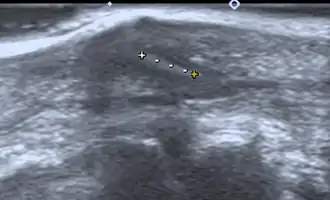

- Medical ultrasonography – used to locate glass, metal, pencil graphite, some plastics, stone, and some types of wood.[6]

Small wooden splinters (1–4 mm) distant from bones are most easily detected by ultrasonography, while CT scan and magnetic resonance imaging have higher sensitivity for those near bones.[7]